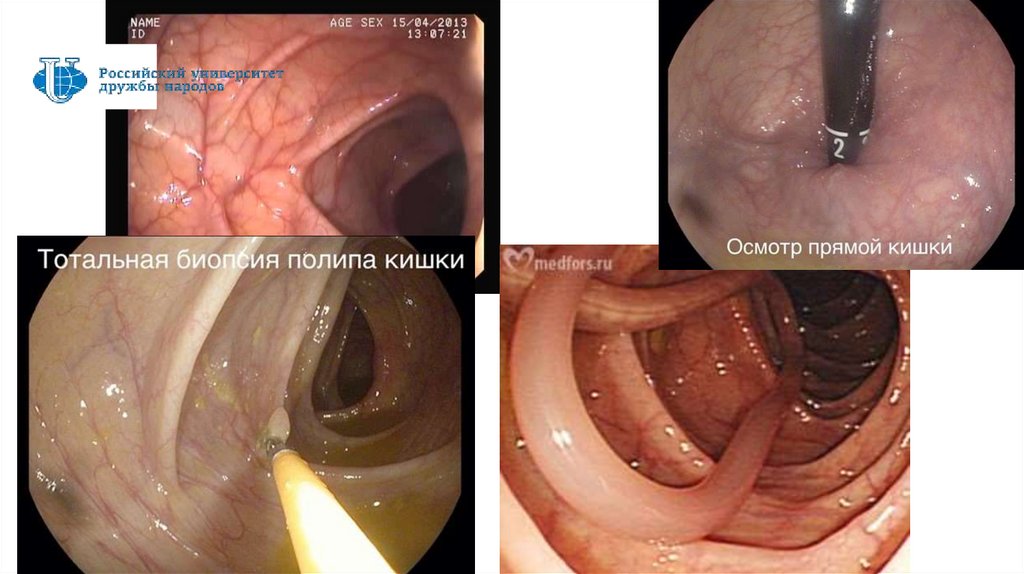

Эндоскопическое исследование

Эндоскопия - метод визуального исследования полостей и каналов тела при помощи

специальных оптических приборов (эндоскопов), снабженных волоконной оптикой.

Преимущества метода эндоскопии неоспоримы — это лечебно-диагностическое исследование:

позволяет определить патологические изменения органа;

позволяет с большой точностью визуально определить локализацию, характер и степень изменений в

слизистой оболочке этих органов;

дает возможность с помощью прицельной биопсии органов получить кусочек пораженной ткани для

гистологического исследования;

используется для введения лекарственного препарата, процедур прижигания, обкалывания;

позволяет удалять инородные тела, полипы;

применяется для диагностического контроля и объективной оценки динамики эффективности лечения.

Эндоскопия толстой кишки

Выделяют:

1. Ректороманоскопия

2. Колоноскопия

Подготовка пациента к ректороманоскопии:

постановка очистительных клизм накануне вечером и

утром в день исследования, последняя - не позднее 2 часов до

исследования. Сама процедура клизмы изменяет рельеф

слизистой оболочки кишечника;

проводится исследование утром в состоянии натощак;

опорожнение мочевого пузыря перед исследованием.

Подготовка пациента к колоноскопии:

- соблюдение бесшлаковой диеты в течение 3 дней до

исследования;

- по назначению врача - прием ферментов и активированного

угля в течение 3 дней до исследования;

- днем накануне исследования прием слабительных — внутрь

или ректально;

- увеличение количества жидкости со второй половины дня

накануне исследования;

- накануне вечером - легкий ужин не позднее 19.00.

- постановка 2-3 очистительных клизм вечером и 2 - 3 утром

вдень исследования, последняя - не позднее 2 часов до

65

- прийти на исследование утром в состоянии натощак.